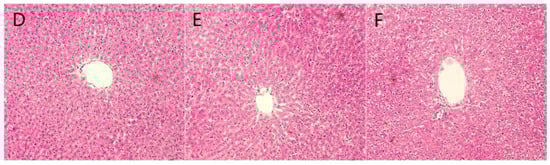

2.6. Staining Results

3.2. Animal Experimentation

4.8. Tissue Embedding Sectioning and Staining